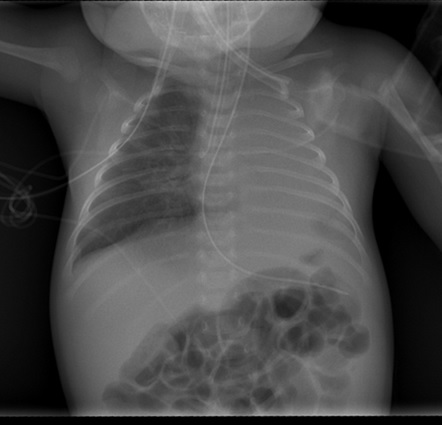

Realizamos RX de tórax porque es una prueba fácil, barata, rápida y que aporta mucha información en la patología pulmonar.

El niño presenta hipoxia y deterioro del nivel de conciencia por lo que se decide proceder con una intubación y se realiza una nueva placa de tórax: